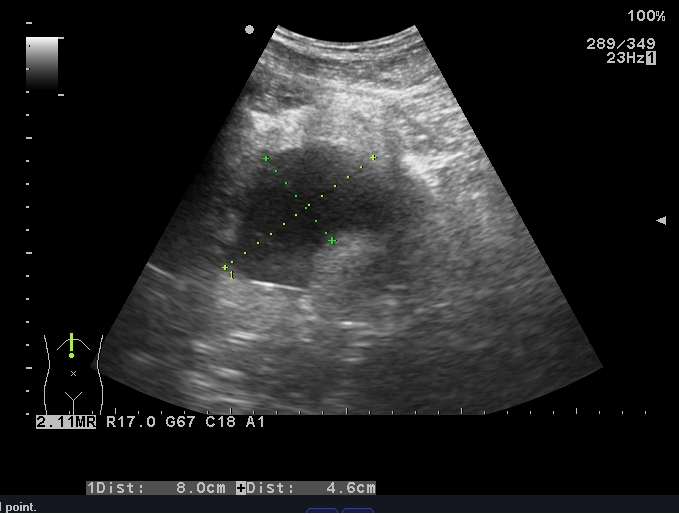

患者取俯卧位,充分暴露手术野,经臀超声扫查了解骶前脓肿情况,确定穿刺点,设计好穿刺路径。常规消毒铺巾,局麻,无菌保护套隔离探头。超声引导下PTC针穿刺直至脓腔边缘,迅速突破囊壁进入脓腔中心(图 3),退出针芯,外接注射器抽吸,见脓液流出(图 4)。将导丝通过针管插入脓腔,固定导丝,拔出针管,刀片沿导丝在臀部做2~3 mm小切口。插入扩张管扩张针道,经导丝将猪尾导管联合支撑管插入脓腔,超声确认穿刺到位(图 5)。拔出导丝,试抽有脓液流出,前推猪尾导管至其前端带侧孔段全部进入脓腔,拔出支撑管,可见液体流出。拉紧导管末端细线使导管尾端呈环状并固定,再次超声检查确定引流管在脓腔内(图 6),用缝线将引流管固定于皮肤上(图 7)。抽出约120 mL脓性液体,生理盐水反复冲洗脓腔,外接无菌引流袋。抽出的脓液取样送细菌培养,并做药物敏感实验。

| 图 3 超声引导下PTC针破壁进入脓腔 |